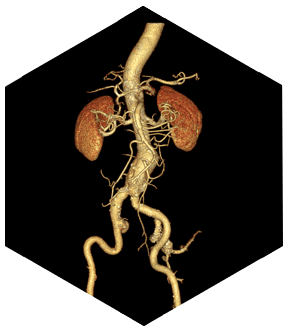

SinoVision Insitum 64 обеспечивает высокое качество изображений и предлагает полный спектр клинических приложений благодаря передовой аппаратной платформе и алгоритмам реконструкции. Высококачественные изображения для различных пациентов обеспечивают точную диагностику при рутинном обследовании.